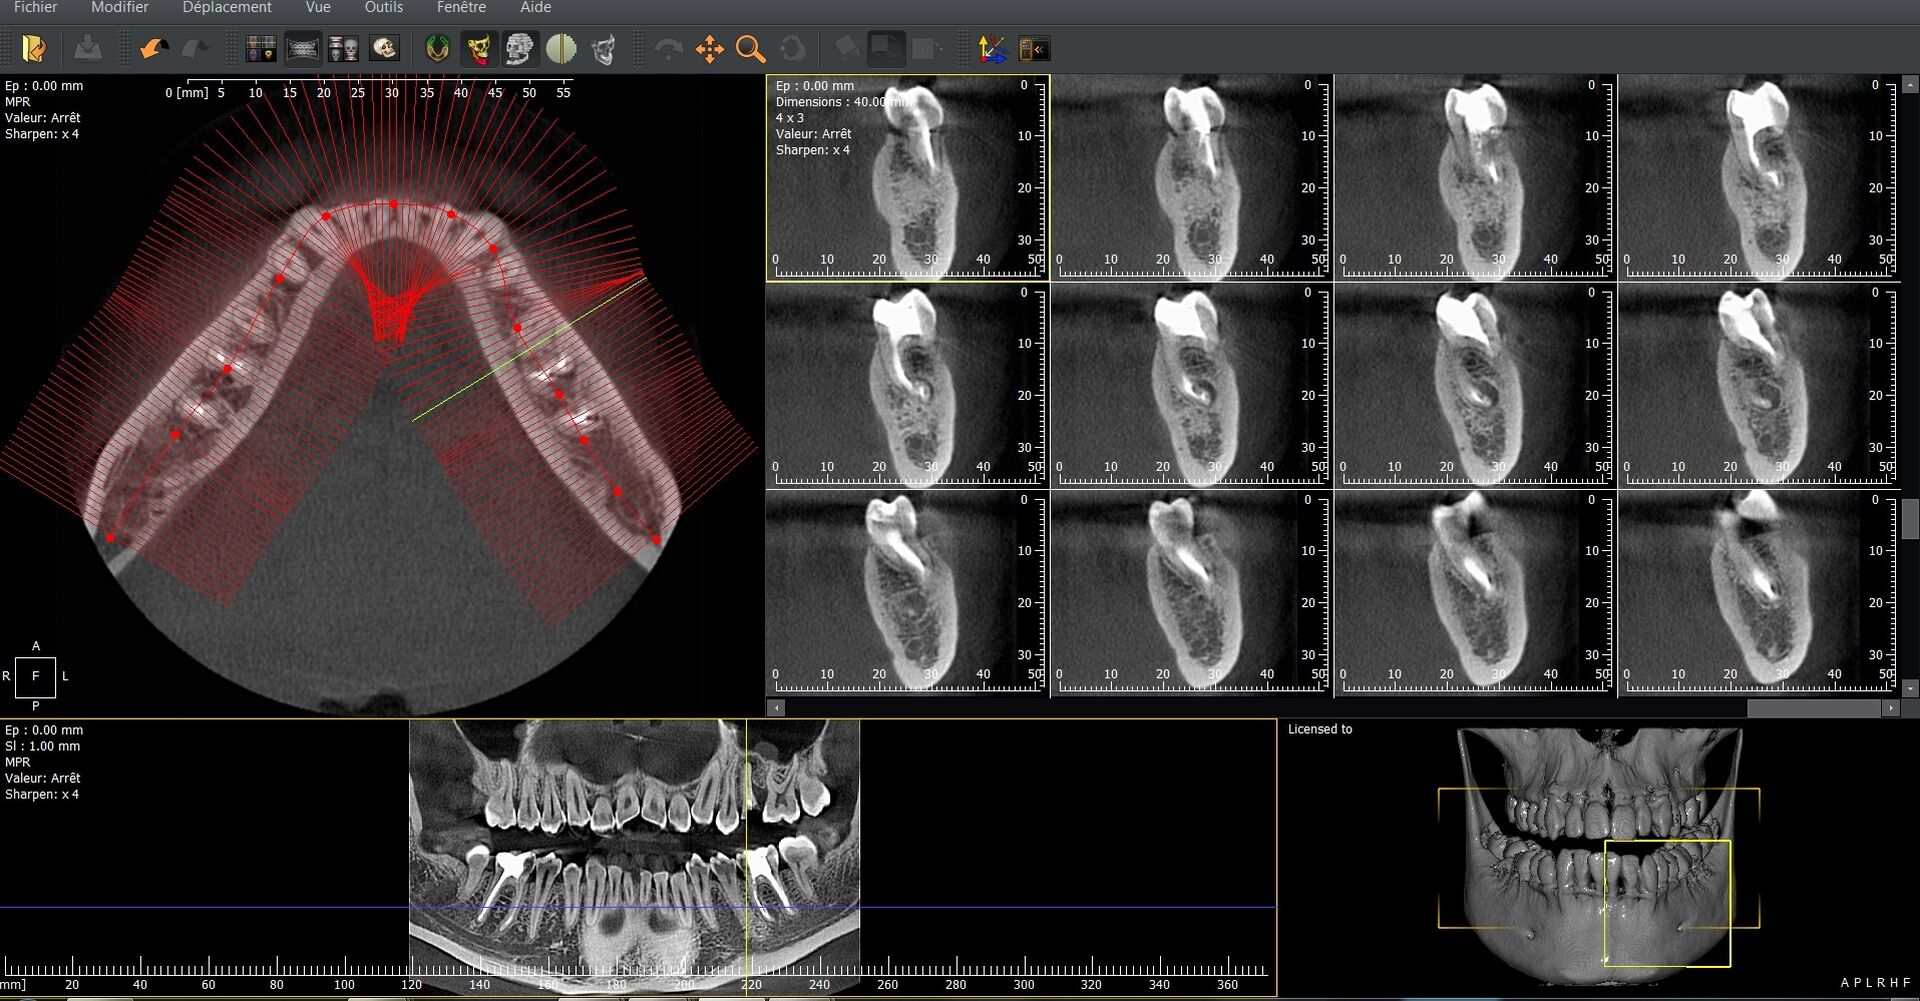

L’I-Max 3D XPRO est un système Cone Beam multifonction 4-en-1 conçu pour fournir une imagerie dentaire ultra-précise dans divers modes : panoramique, 3D, céphalométrie et scan d’objets (modèles en plâtre, porte-empreintes).

La qualité d’image est exceptionnelle, avec une résolution de 70 microns, assurant une finesse diagnostique accrue.

Le champ d’imagerie (FOV) peut être ajusté entre 16×11 cm à 5×5 cm, ce qui permet de cibler précisément la zone d’intérêt et de limiter l’exposition aux rayonnements.

La technologie Super IGZO est au cœur de ce système, avec des innovations telles que le traitement IA (algorithmes de débruitage), le Focus Scintillator pour réduire le bruit et l’algorithme AutoMAR pour atténuer les artéfacts métalliques.  Le positionnement "face à face" améliore le confort du patient et la reproductibilité des prises de vue.

Grâce à sa compacité (empreinte au sol inférieure à 1 m²) et son installation murale ou en colonne, l’appareil peut s’adapter aux contraintes d’espace des cabinets.  L’interface est intuitive, facilitant le passage entre les modes 2D et 3D, et la planification implantaire est supportée par le logiciel QuickVision 3D intégré pour visualiser, simuler et guider les interventions.

En résumé, l’I-Max 3D XPRO combine haute résolution, polyvalence, algorithmes de traitement intelligents et adaptabilité pour optimiser le diagnostic, la planification chirurgicale et l’efficacité clinique au sein des cabinets dentaires modernes.